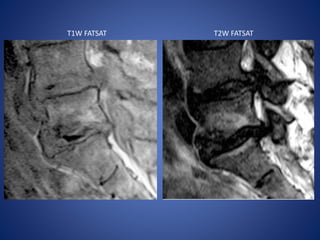

Neuropathic Spine

The neuropathic spine (Charcot spine) displays intervertebral

Neuropathic spine in a 64-year-old man.

T2W FATSAT Contrast-enhanced T1 FATSAT

Neuropathic Spine Diabetes mellitusis now the most common cause of neuropathic disease of the spine. The neuropathic spine (Charcot spine) displays intervertebral space narrowing, vertebral osteolysis and osteosclerosis, subluxations, abrupt curvature, and large endplate spurs.

Neuropathic spine ina 64-year-old man.

• #41 (a, b) Coronal (a) and axial (b) CT images show the classic disordered appearance of a Charcot spine, with intervertebral space destruction, vertebral osteosclerosis, and spondylolisthesis. Disk vacuum phenomena, facet subluxation, arthritis, and massive endplate spurs also are seen.

• #42 (c) Sagittal T2-weighted fat-suppressed MR image reveals fluidlike signal intensity in the disks. (d) Sagittal contrast-enhanced T1-weighted fat-suppressed MR image shows endplate enhancement. The absence of infection was confirmed at biopsy and follow-up clinical evaluation.